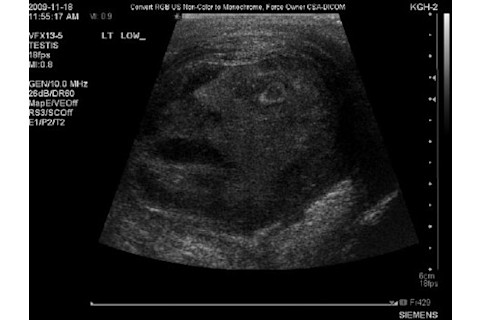

I believe without reservation that this may be the greatest instance of pareidolia of all time: an ultrasound of a man experiencing epididymo-orchitis, or pain and swelling of a testicle:

Having suffered through a similar (if less traumatic) version of this, may I add that the expression on the man's, um, "face" is exquisitely accurate.

Tip o' the codpiece to my Hive Overmind co-blogger Ed Yong on Google+. Original image: Elsevier, Inc.